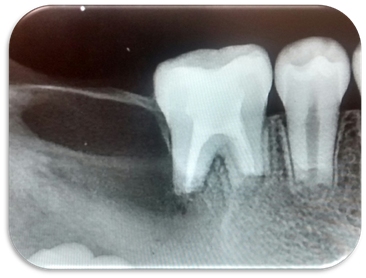

A la exploración física refirió dolor a la percusión y palpación en la pieza 2.1, radiográficamente se observó fractura horizontal en el tercio medio de la raíz (Fig.1), por lo que se decidió ferulizar de la pieza 1.2 a 2.2 (Fig.2).

Fig. 1

Fig. 2

El paciente regresó a los 15 días, se le retiró la férula y se inició el tratamiento de endodoncia anestesiando al paciente, se colocó aislamiento absoluto para posteriormente realizar el acceso a la cámara pulpar con una fresa bola #4 de carburo de tallo largo, se tomó la longitud de trabajo con una lima #20, guiándonos con el localizador de ápices (Root ZX II), la cual fue de 16mm, tomando como punto de referencia el borde incisal (Fig.3).

Se instrumentó hasta la cavometría obtenida desde el borde incisal hasta la línea de la fractura con limas manuales. Se conformó el conducto hasta la lima #70 Flex-R. Se colocó Ultracal (hidróxido de calcio) como medicamento intra-conducto. Se colocó Cavit (ionómero de vidrio) como obturación provisional (Fig.4). Se citó al paciente 7 días posteriores.

Fig. 3

Fig. 4